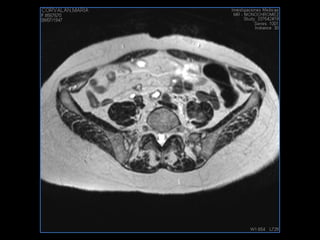

PROTOCOLO pelvis SAG T2, Y FAT SAT (FINOS) AXIAL T1  AX FAT SAT CON   GADOLINIO :  AX T1 Y COR T1 SAT: NO  FASE: RL THK: 3MM  COIL:  GAP: (FACTOR 1.4) 1MM FOV: 40 CM NEX:2 SINCRONIZACION RESPIRATORIA EN 3 O 4 CICLOS ALE